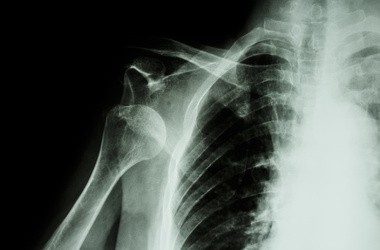

Zmiany w strukturze krążków zachodzą przez całe życie człowieka. Wraz z wiekiem i poddawanym obciążeniom dochodzi do ich spłaszczenia, dehydratacji, a co za tym idzie upośledzenia pełnionych funkcji. Na zdjęciu rentgenowskim mogą pojawiać się zmiany zwyrodnieniowe charakterystyczne dla takiego stanu. Widoczna jest także zazwyczaj wyraźna utrata wysokości oraz zwężenie przestrzeni międzykręgowej jako konsekwencja schorzeń dysku w kręgosłupie.

W pierwszej kolejności zleca się jednak zazwyczaj zdjęcie rentgenowskie, a dopiero potem poszerza diagnostykę. Wynika to wysokich kosztów badania MRI.